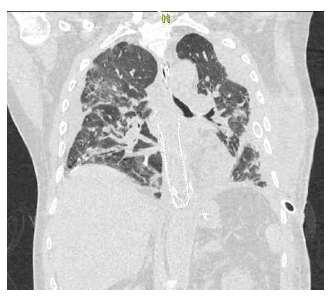

Al día 12 posoperatorio, presentó evolución clínica tórpida, con mala mecánica ventilatoria, requerimiento de intubación orotraqueal, elevación de reactantes de fase aguda y drenaje purulento por tubo a tórax por lo que se realizó nuevo estudio tomográfico que reportó hemotórax izquierdo y hematoma de pared torácica izquierda (Ver Figura 4), con necesidad de escalonamiento antibiótico a meropenem con continuación de linezolid y de reintervención para evaluar dehiscencia de sutura esofágica así como decorticación pulmonar por toracoscopia con pleurectomía parietal y lavado de cavidad.

Además se evidencia el compromiso pulmonar bilateral en patrón de vidrio esmerilado sugestivo de infección por COVID 19.